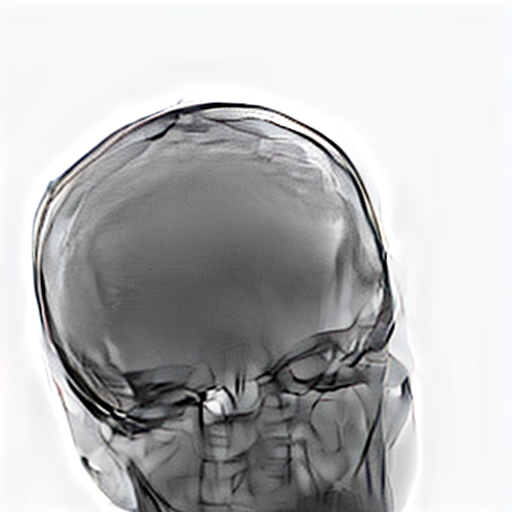

Refer to caption

Figure 1: Overview of MedShift inference. A source image x1x_{1} is first encoded into a domain-agnostic latent representation zτz_{\tau}. This latent lies near a shared manifold across all domains. Then, translation is performed by forward-time sampling conditioned on the target domain label to obtain the translated image x^1\hat{x}_{1}.

During inference, a source image, such as a simulated X-ray (class S), is first encoded into a domain-agnostic latent representation via time integration. Starting from the observed image x1x_{1}, we integrate backward from t=1t=1 to an intermediate time τ(0,1)\tau\in(0,1) under the source domain condition c=Sc=S, yielding the latent representation zτz_{\tau}:

zτ=x1τ1vθ(xt,c=S,t)dt.z_{\tau}=x_{1}-\int_{\tau}^{1}v_{\theta}(x_{t},c=S,t)\,dt. (1)

This intermediate state lies in a shared latent manifold that is approximately aligned across all domains, as shown in Section B. To generate the translated image in a target domain, e.g., a real X-ray at high dose, we then integrate forward from τ\tau to 11, this time conditioning the target domain c=Rc=R:

x^1=zτ+τ1vθ(xt,c=R,t)dt.\hat{x}_{1}=z_{\tau}+\int_{\tau}^{1}v_{\theta}(x_{t},c=R,t)\,dt. (2)

This two-stage process, consisting of encoding and translation, enables faithful domain transfer while preserving essential anatomical content. Figure 1 illustrates this conditional transport mechanism between domains.